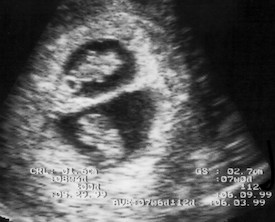

除年龄外,尚无数据决定哪些人互为拮抗者。这在性别、人种、族裔、出生地、或身心特征上完全随机。不过,互为拮抗者的两人出生时间相差均不超过三周:目前理论认为,SCP-6180的链接是在受精后10 - 85天的胚胎中形成的。需注意,这种链接通常在阑尾发育之前形成。